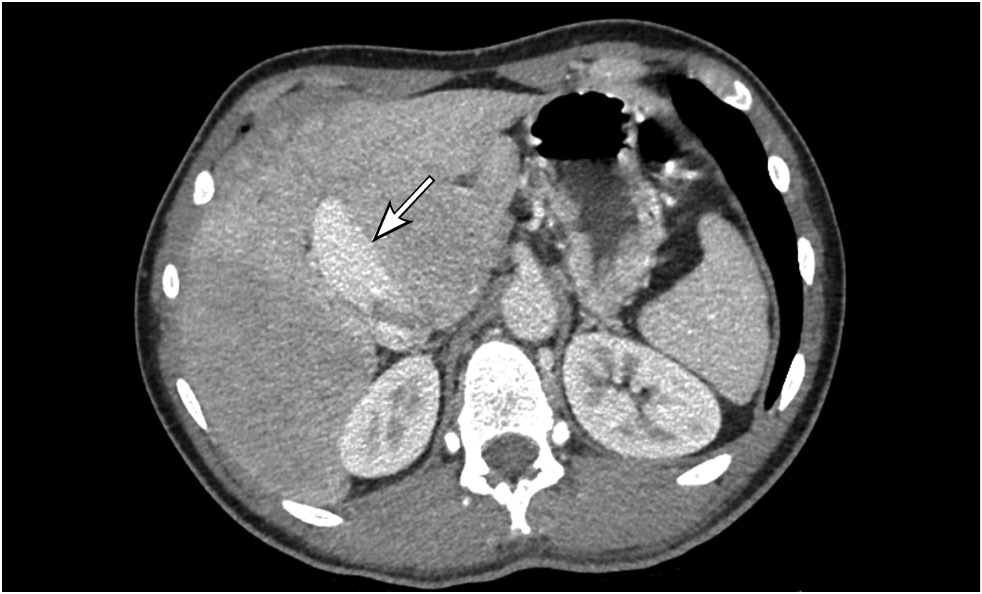

Contrast-enhanced abdominal computed tomography (CT) with multiplanar reconstruction revealed that the splenic (12 mm in diameter (Figure 1)) and superior mesenteric veins fused together, forming a portal vein conduit dilated to 28 mm in diameter (Figures 2 and 3), flowing directly into the inferior vena cava (IVC), bypassing the porta hepatis (Figure 4). Moreover, moderate liver and spleen enlargement and weak heterogeneous contrast enhancement of the liver parenchyma were noted. The findings were consistent with Abernethy malformation type Ib.

Fig. 3. Contrast-enhanced CT, portal phase, axial view. Portal vein conduit (white arrow).